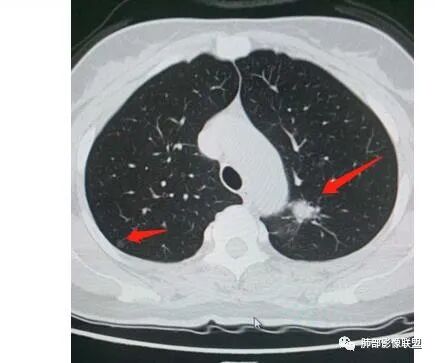

一、先讨论GGN吧

1、密度?MGGN?PGGN?

2、边界?清?不清?

3、有无收缩力?有胸膜牵拉?毛刺?

4、血管连通 移动:3型?4型?

两条都进入,相互交通-4

常规判断还需要大小、CT值

大家诊断啥?

二.左肺上叶前段磨玻璃结节:

该结节较大,边界清楚,小叶间隔阻挡特征相当明显,微浸润腺癌的诊断几乎没有争议!

三.右肺上叶胸膜下结节及左肺上叶血管旁结节,尽管都是磨玻璃密度,但都比较小且边缘特征不明显,恶性征象未显露,处置并无特殊,定期复查!